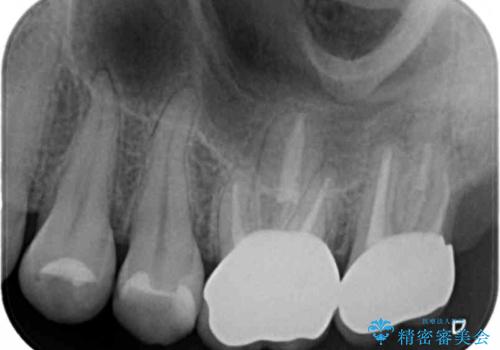

・咬合機能の回復 →セラミッククラウンの製作

深い虫歯・根尖性歯周炎・咬合機能の回復の問題を解決し良好な治療結果を得ることができました。